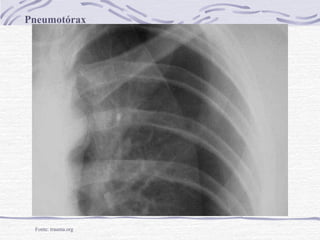

Pneumotórax

Fonte: trauma.org